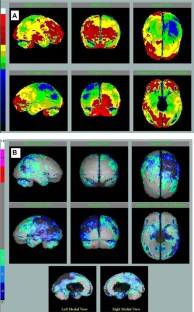

Klunk WE, Koeppe RA, Price JC, Benzinger TL, Devous Sr MD, Jagust WJ, et al. The Centiloid Project: standardizing quantitative amyloid plaque estimation by PET. Alzheimers Dement. 2015;11:1–15.

- 55.

Rowe CC, Jones G, Doré V, Pejoska S, Margison L, Mulligan RS, et al. Standardized expression of 18F-NAV4694 and 11C-PiB β-amyloid PET results with the Centiloid Scale. J Nucl Med. 2016;57:1233–7.

- 56.